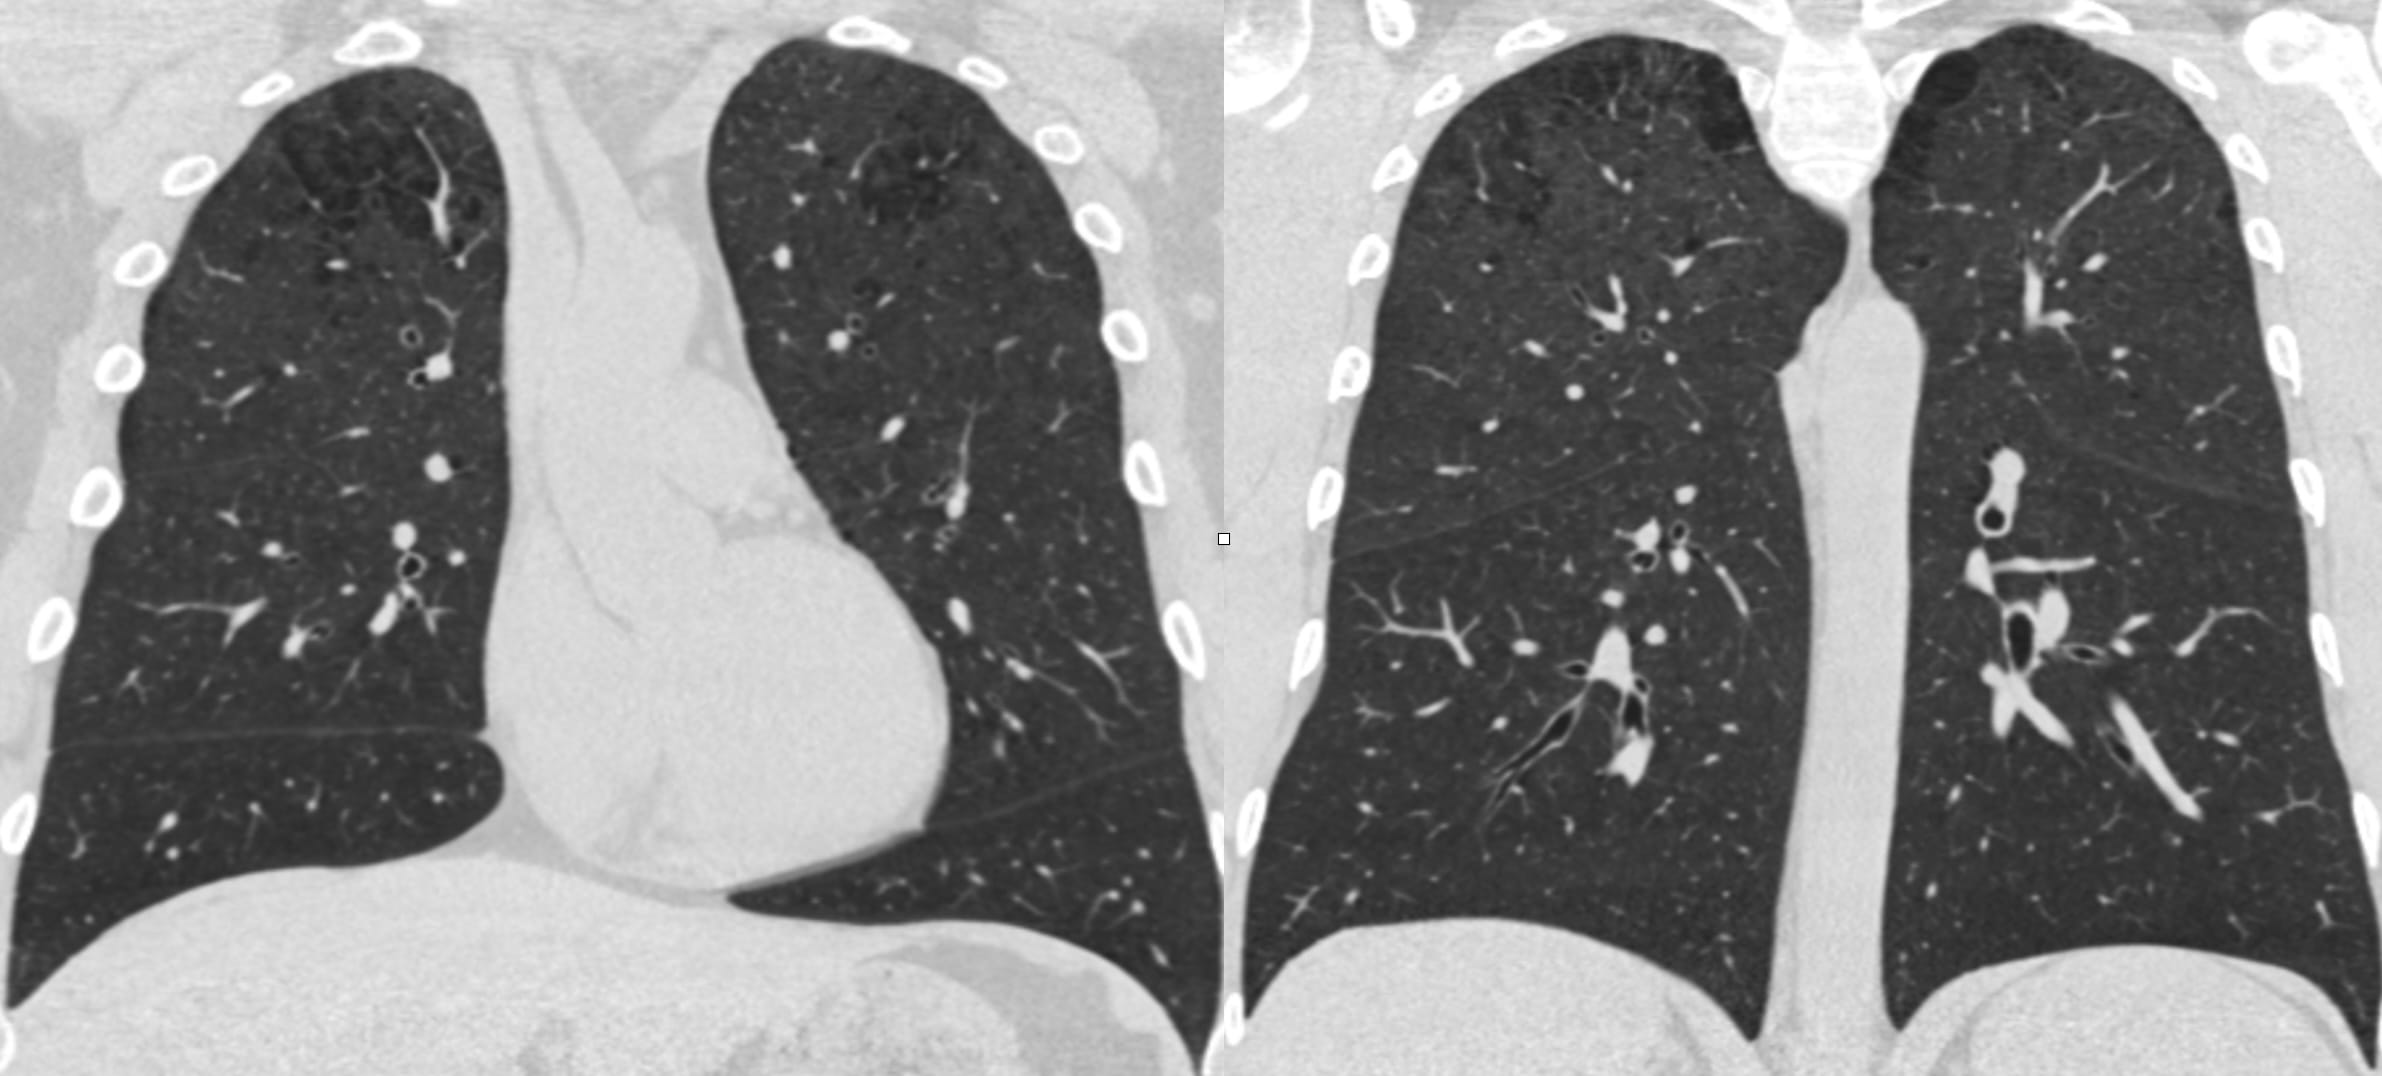

Airway-dominant phenotype

Emphysema-dominant phenotype

Mixed phenotype

We can make these distinctions on CT.

The effects on lung volumes correlate well with functional capacity and symptoms